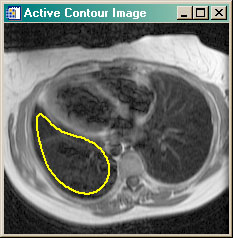

- ACTIVECONTOUR Active contour (or snake) example program. Uses GVF Active Contouring algorithm.